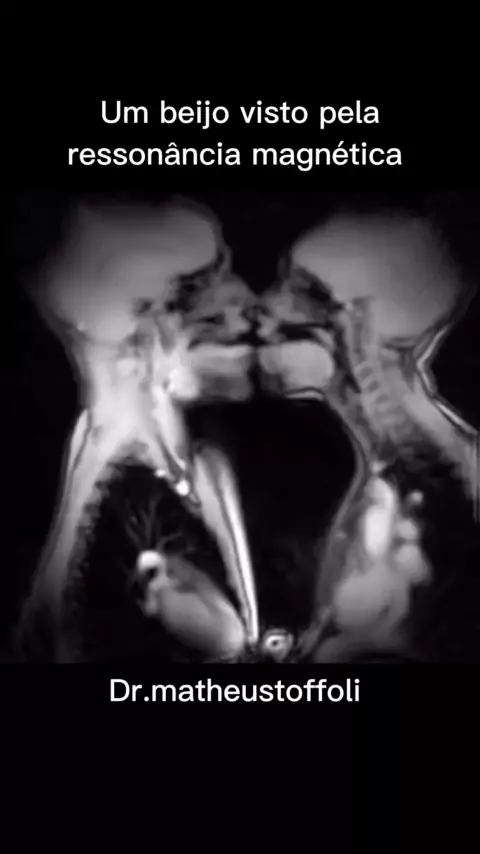

Dr.MatheusToffoli

#Eleições2022 #meucabelominhacoroa #rendaextra #avioesfantasy #medicina